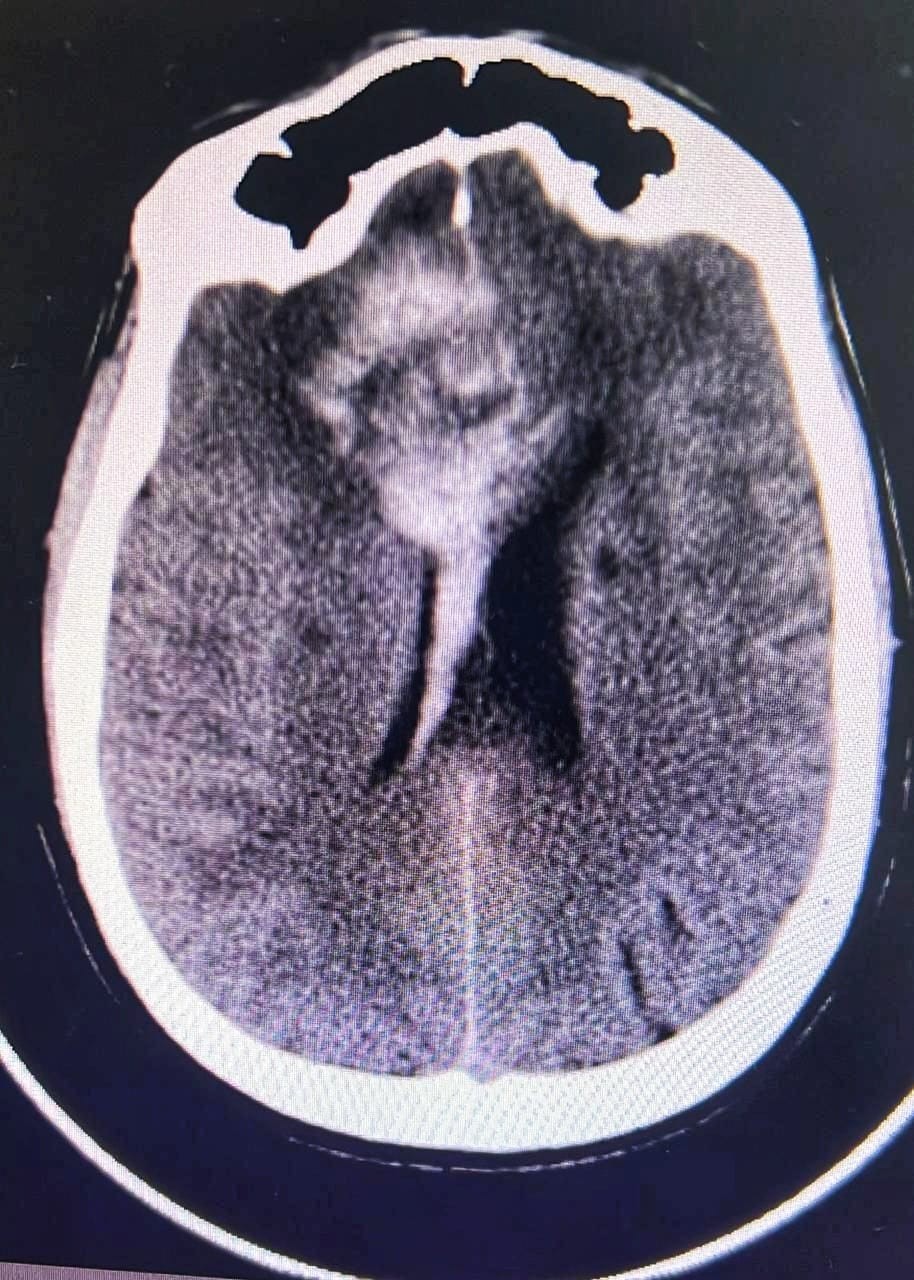

وتم اجراء الفحوصات اللازمة له وتبين وجود تمدد في الأوعية الدموية في الفص الأيسر من الدماغ مسببا انفجار الشريان الوسطي الدماغي الأيسر  .

وأوضح الدكتور أنور الهاشم رئيس قسم جراحة المخ والأعصاب والعمود الفقري ان الفحوصات أظهرت تلفا في مركز الحركة في الفص الأيسر ونقصاً في التروية الدموية مهدداً بفقدان وظائف هذا الفص بشكل شبه دائم .

مشيرا انه وبعد تقييم الحالة قرر الفريق الطبي اللجوء إلى تقنية إغلاق النزيف بالقسطرة لإعادة فتح التروية الدموية  وذلك بواسطة فريق الأشعة التداخلية حيث تم الدخول عبر شريان الفخذ وتوجيه القسطرة إلى الأوعية المصابة باستخدام تقنية مزدوجة لاغلاق النزيف بدعامة معدنية .